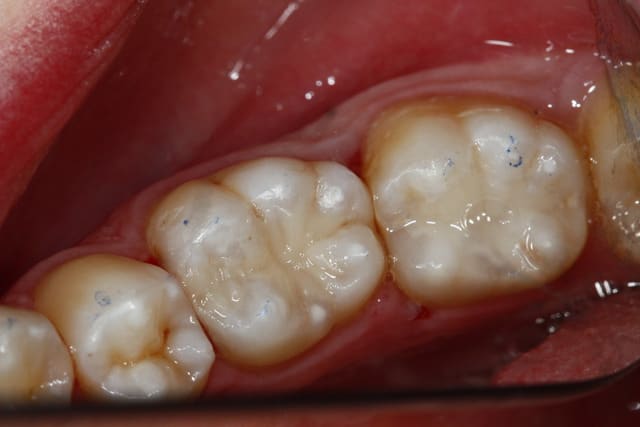

On relance, 2 compos tous frais, c'est basique mais ça me fait plaisir, en 35 minutes avec le détartrage on est presque au taux horaire, pas de stress...

Photos un peu floues, j'ai prêté mon miroir occlusal, désolé.